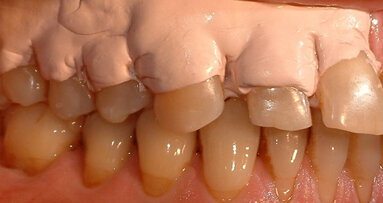

Un paziente di 56 anni non fumatore viene riferito alla nostra osservazione per il trattamento della parodontite. Dopo aver effettuato la diagnosi (parodontite generalizzata Stadio III, Grado C) il paziente è sottoposto a due sedute di scaling sopra gengivale (step 1) e successivamente a 4 sedute di debridement sotto gengivale effettuato con strumenti ultrasonici e manuali (step 2). Al momento della rivalutazione si registra un miglioramento degli indici di placca e di sanguinamento (FMPS e FMBS ≤ 20%) e una riduzione di tutte le tasche parodontali (PD<4 mm) in ciascun sestante a eccezione del secondo sestante. In questa regione si registra una tasca residua con PD = 6 mm a carico dell’elemento 1.1, associata a un riassorbimento osseo radiografico prevalentemente orizzontale (Figg. 1, 2). Considerando il miglioramento di tutti i parametri e degli indici parodontali e la presenza di una tasca con PD = 6 mm a carico di un solo elemento dentario si decide di ritrattare l’elemento 1.1 con terapia non chirurgica (step 3). La nuova ristrumentazione è stata effettuata seguendo il protocollo Clean&Seal che prevede l’associazione di ipoclorito di sodio stabilizzato con amminoacidi e acido ialuronico reticolato ad alto peso molecolare in combinazione con il debridement sotto gengivale. Dopo anestesia locale, è stato applicato all’interno della tasca l’ipoclorito di sodio stabilizzato con amminoacidi e lasciato agire per circa 60 secondi (Fig. 3). Successivamente è stata effettuata la strumentazione sotto gengivale mediante l’utilizzo di strumenti ultrasonici e manuali (Figg. 4, 5). Alla fine della procedura di strumentazione, nella tasca è stata effettuata un’irrigazione con soluzione salina sterile e la procedura di applicazione di ipoclorito di sodio e di strumentazione meccanica è stata ripetuta per 4 volte. Un fattore critico per garantire un risultato migliore è di evitare di instillare qualsiasi soluzione a base di clorexidina nella tasca, in quanto inibisce l’adesione cellulare. Alla fine del trattamento meccanico è stato inserito l’acido ialuronico reticolato ad alto peso molecolare all’interno della tasca per stabilizzare il coagulo e accelerare la guarigione (Fig. 6). Il controllo clinico è stato effettuato dopo 6 settimane dal trattamento con completa chiusura della tasca (Fig. 7).